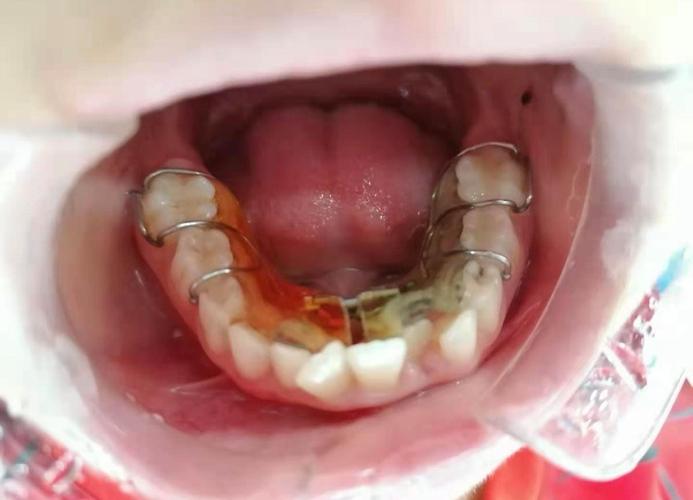

正畸后牙齿斜的首要原因与“保持器”密切相关,牙齿移动后,牙槽骨需要时间重建,牙周组织(如牙龈、牙周膜)也需要时间适应新的位置,这个过程被称为“牙骨改建稳定期”,通常需要1-2年,若在此期间未严格佩戴保持器,牙齿可能会因周围肌肉(如舌肌、唇肌)的异常力量、咀嚼时的咬合干扰,或自身重力作用而逐渐移位,夜间不戴保持器,白天仅佩戴数小时,无法对抗夜间牙齿的自然漂移趋势,久而久之便会导致牙齿倾斜,保持器本身也存在损耗问题,如透明保持器因长期佩戴变松、钢丝保持器的钢丝变形等,无法有效固定牙齿,也会引发移位。

针对上述原因,解决正畸后牙齿斜问题需“对症下药”,若因保持器问题,首先需检查保持器是否贴合,若已变形或松脱,需及时重新制作,保持器需全天佩戴(除吃饭、刷牙外)至少6个月,之后过渡到夜间长期佩戴,甚至终身佩戴,对于牙周问题患者,需先进行牙周系统治疗(如洁治、刮治、牙周手术等),控制炎症,改善牙周环境,必要时结合牙周夹板固定松动牙齿,咬合干扰导致的牙齿斜,需进行咬合调整,如调磨过高牙尖、制作咬合板,或通过修复治疗(如牙冠、嵌体)恢复咬合平衡,生长发育因素引发的,需定期监测颌骨变化,必要时在成年后进行二次矫正,若矫正方案或执行存在缺陷,则可能通过隐形矫正或固定矫正进行精细调整,重新排齐牙齿并建立稳定咬合。

为预防正畸后牙齿斜,患者需做到:严格遵循医嘱佩戴保持器,定期复查保持器情况;保持良好的口腔卫生,定期进行牙周检查和治疗;避免夜磨牙、偏侧咀嚼等不良习惯,必要时佩戴夜磨牙垫;矫正后定期复查(通常建议每3-6个月一次),及时发现并处理潜在问题。